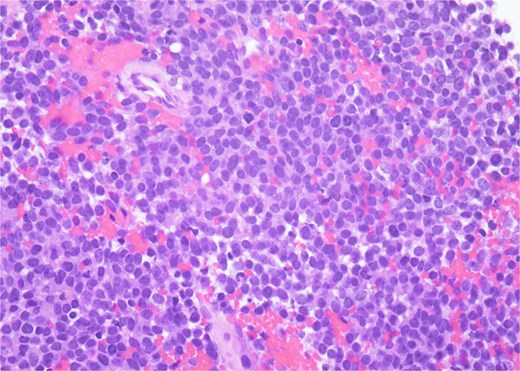

Histopathology revealed small, round, blue cells (Fig. 2), and other findings consistent with ES (Fig. 3).

H&E, 40×. The neoplastic cells have scant cytoplasm, finely stippled chromatin, and inconspicuous nucleoli. At high power, mitotic figures and apoptotic debris are visible.